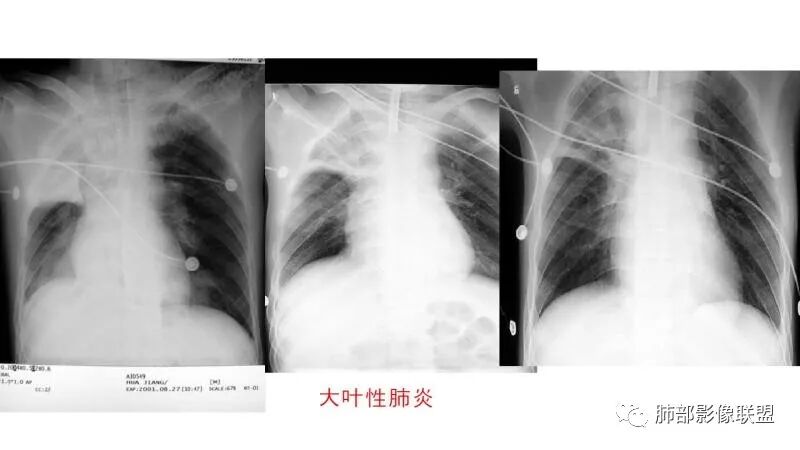

一般细菌性肺炎大叶性沿气道分布

大叶性肺炎是外周向中心的,与胸膜垂直的,沿着气道方向,隐球菌是平行胸膜的,我感觉是肺小叶内的肺泡起源

细菌性肺炎是沿着支气管往周围肺泡散开,内朝外,沿着叶段分布,受到支气管管辖,呈扇形,与支气管长轴平行,与胸膜垂直,隐球菌就是外朝内,外就是肺小叶内的肺泡,外周的。

肺小叶。他就是一个个肺小叶的融合,胸膜平行,和病毒一样。只是病毒在间质,是肺小叶分布的毛玻璃。隐球菌是肺实质,肺泡,肺小叶的实变。

这个病变也不是一个起源中心,胸膜下,多发结节状、实变影。而大叶性肺炎多数由内-外大片状。所以是肺实质多发融合病变。单纯从影像上,还是比较符合隐球菌特点,胸膜下,多发、多中心,相互融合(兄弟齐心)。

大叶性肺炎就是累及肺泡,然后沿着肺泡孔蔓延,不按叶段分布,跟支气管也没什么关系,是外朝内,不是内朝外吧?

大叶性肺炎,非节段分布,外朝内

但是大叶性肺炎,是有叶段的束缚,平行于支气管。他发生是以中央为核心散开。不是外周一个个肺小叶融合。位置上一个高位,一个很末梢

大叶性肺炎一定受叶、段的局限。充其量周围有一些蔓延出来。肺链,金葡都是。金葡和曲霉的一个鉴别点:一个从内向外,一个从外向内。3型曲霉-农村包围城市。金葡-城市向农村发展。